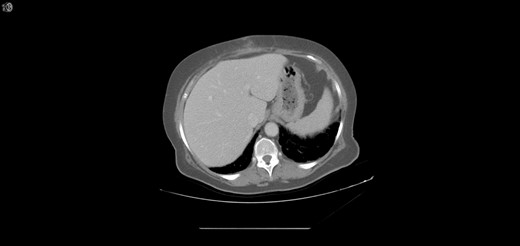

A 64-year-old female presented to the emergency department with a chief complaint of epigastric pain and nausea lasting 24 h. Relevant medical history includes congestive heart failure, interstitial lung disease, chronic obstructive pulmonary disease and prior open cholecystectomy. Home medications included a course of methylprednisolone for acute exacerbation of lung disease. On exam, her abdomen was tender and distended. Labs showed leukocytosis with normal lactate level. Figures 1 and 2 show abdominal computed tomography (CT) without contrast, significant for small bowel obstruction with intramural small bowel pneumatosis and extensive portal venous gas (PVG) within the left hepatic lobe. Emergent laparotomy was performed for acute abdomen. Exploration of the abdominal viscera revealed no evidence of inflammation, necrosis or perforation. The patient continued to have pain after surgery. Upper endoscopy was performed, revealing a non-perforated gastric ulcer which was treated with medical management until the pain resolved.

Extensive portal venous gas noted in the left lobe of the liver during the first admission. Laparotomy was negative for bowel ischemia.